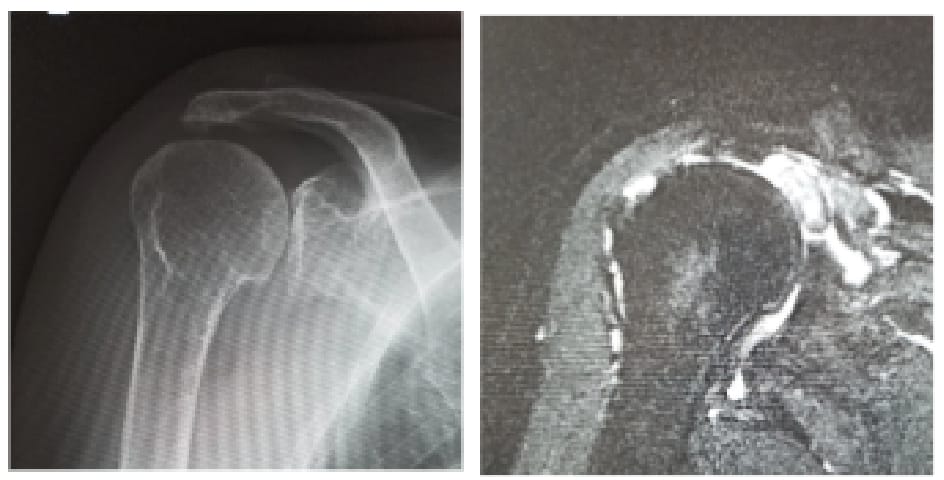

腱板断裂症性肩関節症や修復困難な肩腱板断裂に対しては、リバース型人工肩関節置換術を実施しています。良好な機能回復を得るためには、正確かつ再現性の高いインプラント設置が不可欠です。当班では、CT 画像を用いた術前3Dプランニングに加え、術中ナビゲーションシステムなど最先端の技術を活用することで、より高精度な手術を実現しています。

腱板断裂症性肩関節症